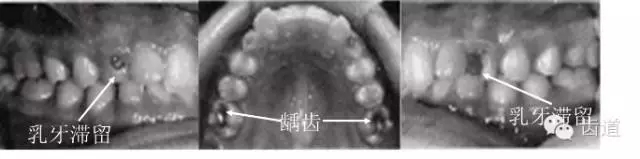

4.乳牙、恒牙萌出及替換:

如乳牙早失或滯留,恒牙早萌或早失。

5.齲齒、牙周病及口腔衛(wèi)生情況。

45.webp.jpg